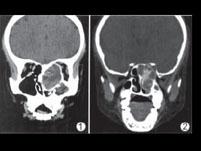

问题 动脉瘤样骨囊肿CT检查一般不会出现()

选项 A.病变多呈囊状膨胀性骨破坏、 B.病变多呈溶骨性骨破坏、 C.破坏区内一般可见多个含液囊腔、 D.破坏区与正常骨交界区可有硬化、 E.囊腔间隔为软组织密度,并可见钙化或骨化、

答案 B